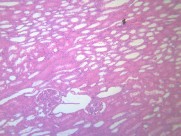

肾小管renal tubule 与肾小囊壁层相连的一条细长上皮性小管,具有重吸收(reabsorption)和排泌作用(secretion).肾小管按不同的形态结构,分布位置和功能分成三部分;近端小管,细段和远端小管。肾小管在肾髓质中。